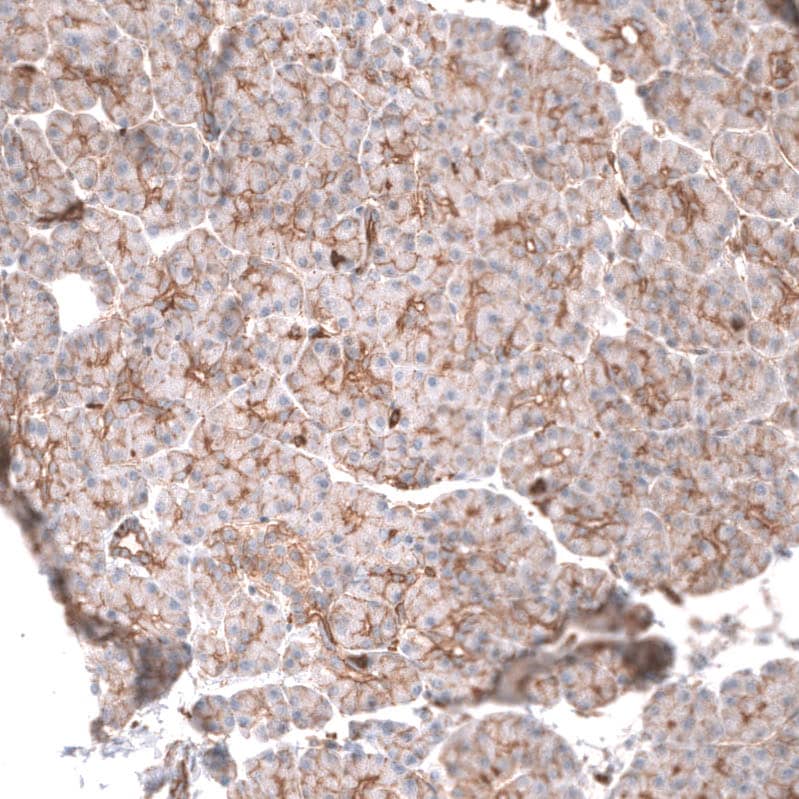

Staining of human pancreas shows moderate membranous positivity in exocrine glandular cells.